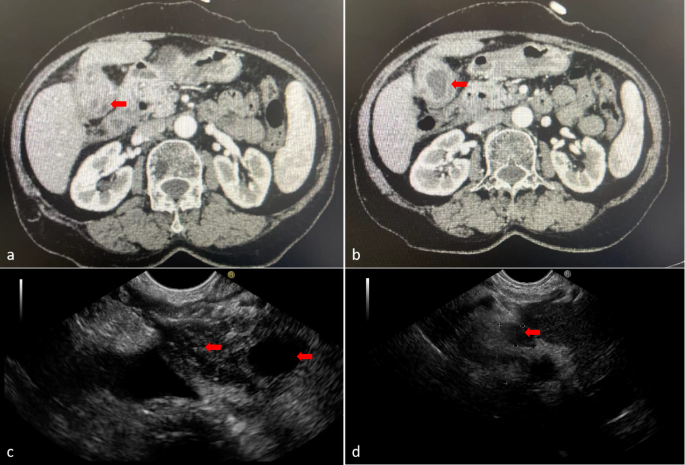

All biopsies in the EUS group were performed by a single endoscopist, whereas those in the PTGB group were conducted by a single ultrasonologist. Both operators had experience with more than 500 cases. Patients received analgesic premedication; 15 mg of pentazocine was administered for PTGB, while a combination of either 35 mg of piperidine hydrochloride or 7.5–15 mg of pentazocine with 2–5 mg of midazolam was used for EUS-FNA. PTGB was guided by abdominal ultrasound using the Hitachi Preirus system, which involved a transhepatic approach and puncturing the tumor with 17-18G needles. EUS-FNA was performed using a Pentax 3870UTK endoscope and a Hitachi Preirus ultrasound processor. 22G aspiration needles were selected at the operator’s discretion (Fig. 1). Rapid on-site cytological evaluation was performed.

(a) Abdominal contrast-enhanced CT showed solid mass in gallbladder; (b) Abdominal contrast-enhanced CT showed uneven thickening of gallbladder wall; (c) Endoscopic ultrasound showed mass in gallbladder (indicated by left arrow) and gallbladder lumen (indicated by right arrow); (d) Endoscopic ultrasound showed lymph node (indicated by arrow).